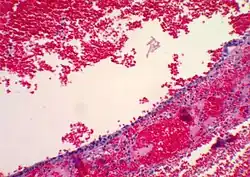

| Functional cyst | Follicular cyst |

|